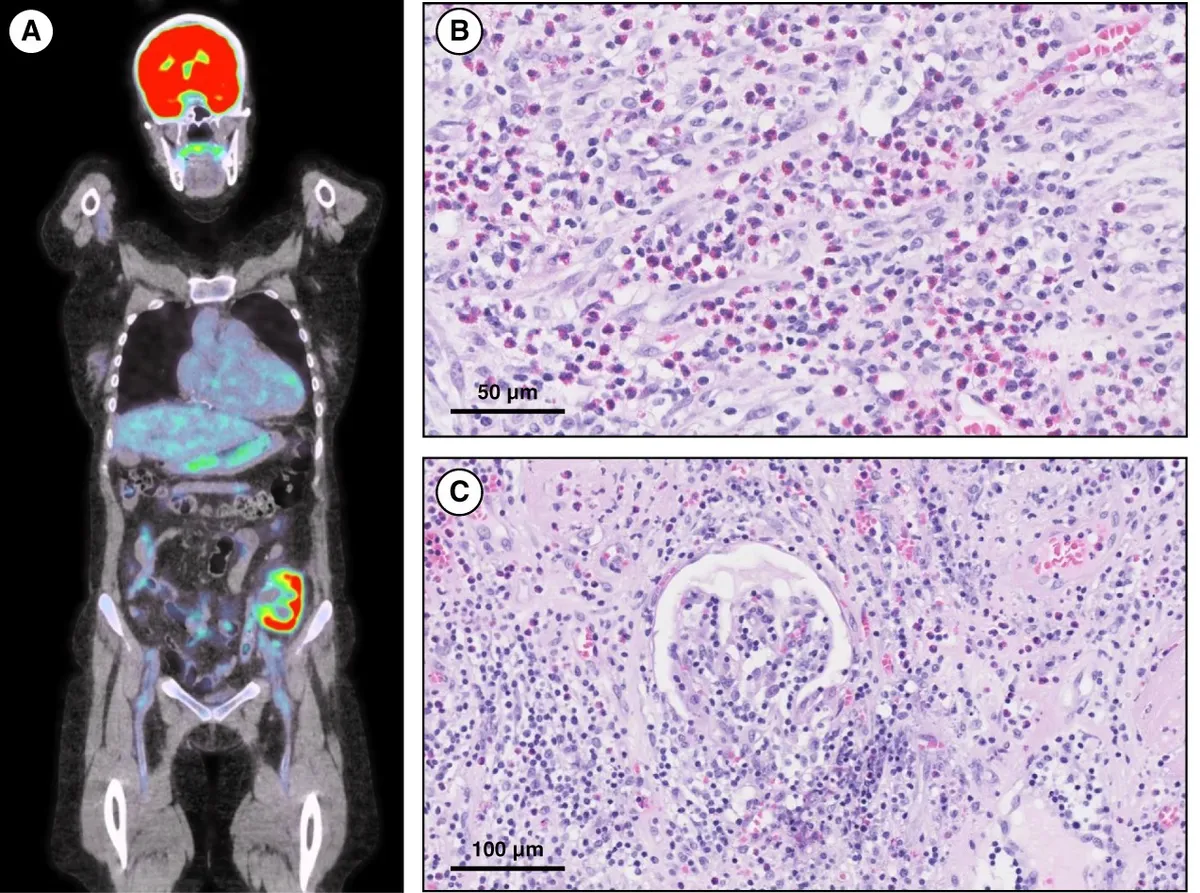

Uma causa incomum de hematúria glomerular intermitente!

Hematúria pós infecção, caso clínicos para auxiliar no entendimento de causas glomerulares comuns e raras...

Highlights ASN 2025: Novas Fronteiras em IgA, descontinuação de Hemodiálise e o uso do Ômega-3 nos dialíticos